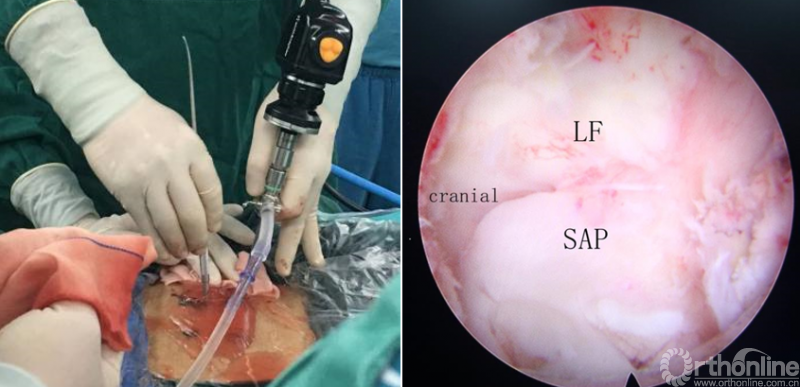

第一步“定”:X线定位在上位椎体下关节突下三分之一部;

第二步“辨”:镜下辨别下关节突关节囊;

第三步“凿”:凿除部分下关节突,显露上关节突及黄韧带;

第四步“分”:分离上关节突及黄韧带;